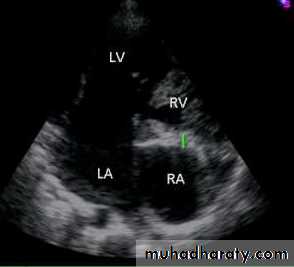

Ebstein anomaly consists of downward displacement of an abnormal tricuspid valve into the right ventricle.

The right ventricle is divided into 2 parts by the abnormal tricuspid valve: the 1st, a thin-walled “atrialized” portion, is continuous with the cavity of the right atrium; the 2nd, often smaller portion consists of normal ventricular myocardium.

RV output is decreased due to a combination of the poorly

functioning small right ventricle and tricuspid valve regurgitation,

Echo is diagnostic and shows the abnormalities.